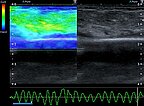

In der Ultraschall-Elastographie kann die mechanische Härte des Tumors farbkodiert dargestellt werden (links im Bild), rechts im Bild das zugehörige B-Bild. In der Farbkodierung wird hartes Gewebe blau dargestellt, mittelhartes grün und weiches Gewebe rötlich. Der Tumor selbst ist mittelhart bis eher etwas weicher (grün) als das umgebende Gewebe (blau).